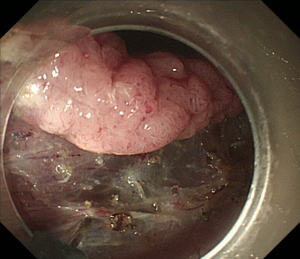

| 【大腸ESD】 |

Hook knifeという粘膜下層剥離術専用の電気メスを用いて癌のすぐ下の層を剥離しています。大腸や直腸は消化管の壁が非常に薄いため、穿孔(腸壁に穴を開ける)させないように注意深く剥離を進めます。 |